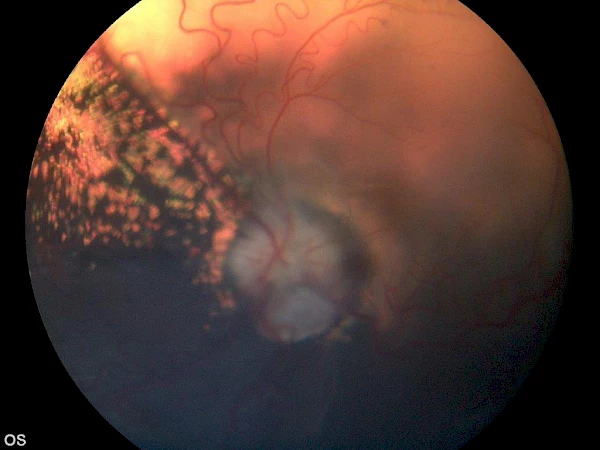

angeborene Netzhautablösung, ein geeigneter Kandidat für eine erfolgreiche Netzhautoperation angeborene Netzhautablösung, ein geeigneter Kandidat für eine erfolgreiche Netzhautoperation

vor Operation vor Operation